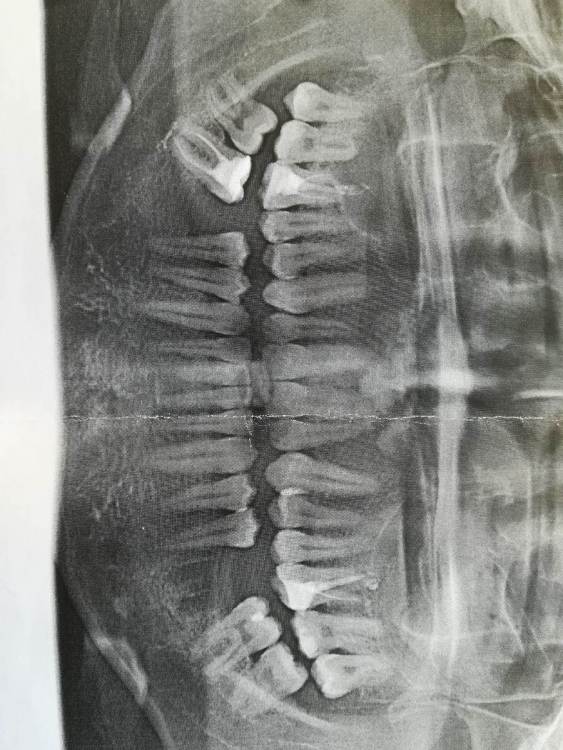

Здравствуйте. Нужно мнение специалистов.  После удаления зуба прошло  5 месяцев, планирую поставить имплант AnyRidge Нижний 19 зуб. Был на консультации у двух стоматологов, один сказал что можно ставить имплант и проблем он не видит, а второй говорит что костная ткань где лунки после удаления зуба еще  не зарасла и нужно подождать  три месяца.  Десна полностью зажила. Так мой вопрос - Можно ли сейчас ставить имплант, или действительно нужно ещё подождать пока костная ткань зарастет?  Если ждать ещё 3 месяца то не атрофируется ли кость и не просядет десна?  Заранее спасибо. IMG_20210910_134042.thumb.jpg.4d001b1960b0684054ba0f3f2aa03bcf.jpg